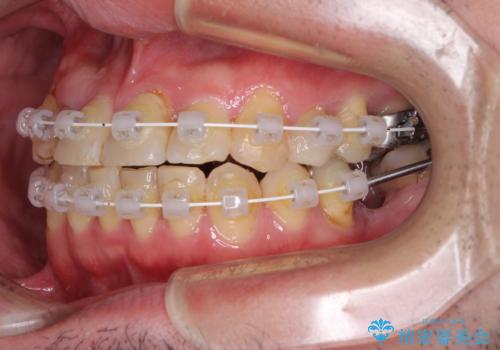

矯正治療でインプラント埋入を行い、矯正治療後に気になる前歯と合わせてオールセラミッククラウンによる補綴治療を行うこととしました。

骨造成や歯肉移植など、治癒期間の長い処置を必要としたため治療期間は長くなりましたが、安定した咬み合わせと整った歯列となり、患者様には大変満足していただきました。